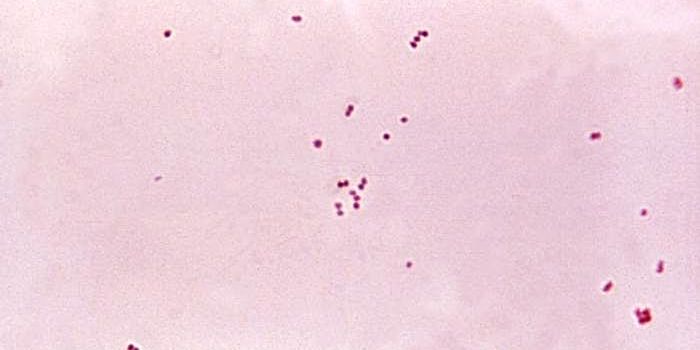

FEB 23, 2019Health & MedicineFacklamia species are Gram-positive, facultatively anaerobic bacteria that present a challenge for clinical labs to ...